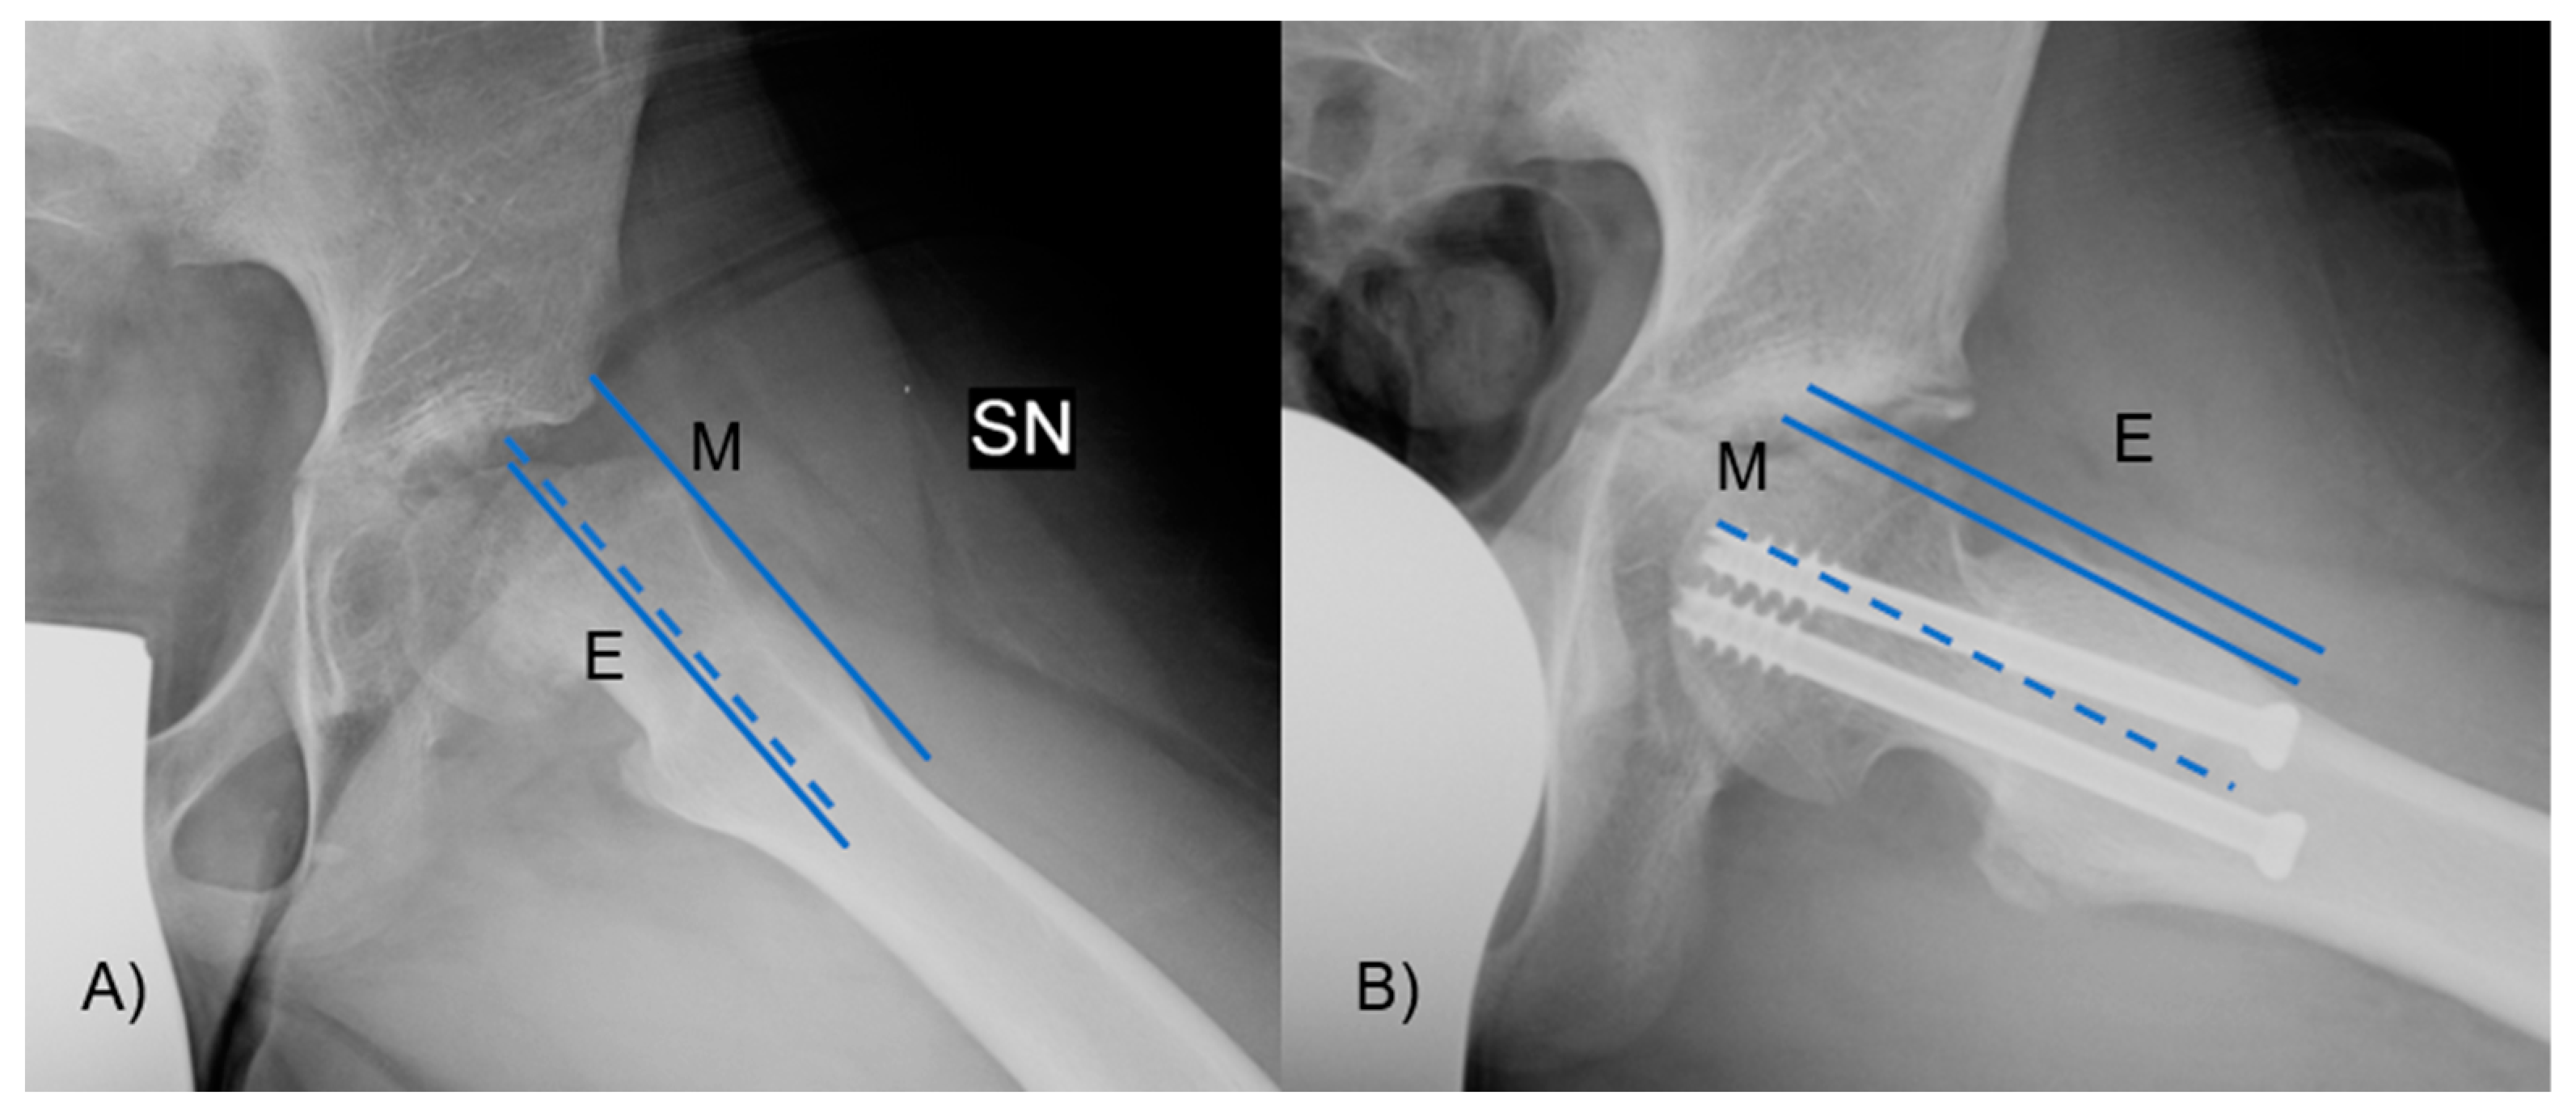

The α angle was measured between the axis of the femoral neck and the line extending from the central part of the femoral head to the location where the distance from the central point of the femoral head to the outer edge surpassed the femoral head’s radius (Figure 4). Slippage of the femoral head will occur at a higher α angle.

Figure 4.

The α angle was measured between the axis of the femoral neck and the line from the center of the femoral head to the point where the distance from the center of the femoral head to the peripheral contour of the femoral head exceeded the radius of the femoral head. In figure (A), there is an angle greater than 90°, with neck deformity, while in figure (B), the angle and the deformity are lessened.